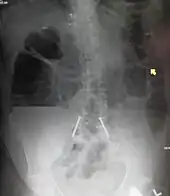

| Upright abdominal X-ray demonstrating a small bowel obstruction. Note multiple air fluid levels. | |

Causes of bowel obstruction include adhesions, hernias, volvulus, endometriosis, inflammatory bowel disease, appendicitis, tumors, diverticulitis, ischemic bowel, tuberculosis and intussusception.[1][2] Small bowel obstructions are most often due to adhesions and hernias while large bowel obstructions are most often due to tumors and volvulus.[1][2] The diagnosis may be made on plain X-rays; however, CT scan is more accurate.[1] Ultrasound or MRI may help in the diagnosis of children or pregnant women.[1]

Radiological signs of bowel obstruction include bowel distension and the presence of multiple (more than six) gas-fluid levels on supine and erect abdominal radiographs. Ultrasounds may be as useful as CT scanning to make the diagnosis.[17]